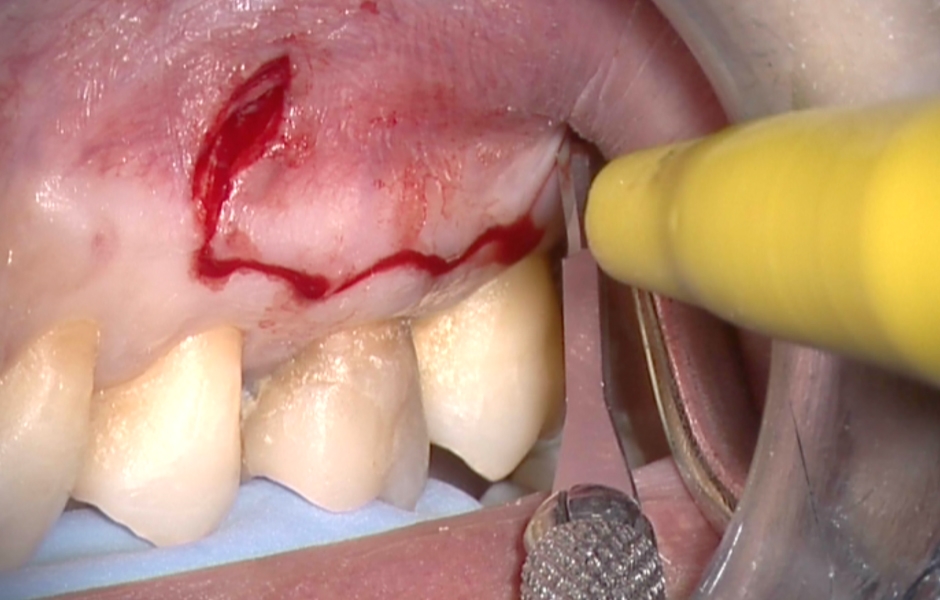

Obr. 1.2: Submarginální incize.

Pro incizi měkkých tkání používáme mikrochirurgickou čepel a elevace i retrakce laloku musí být maximálně šetrná. Veškerý pooperační diskomfort pacienta je úměrný tomu, jak jemně operatér s chirurgickým lalokem zachází.